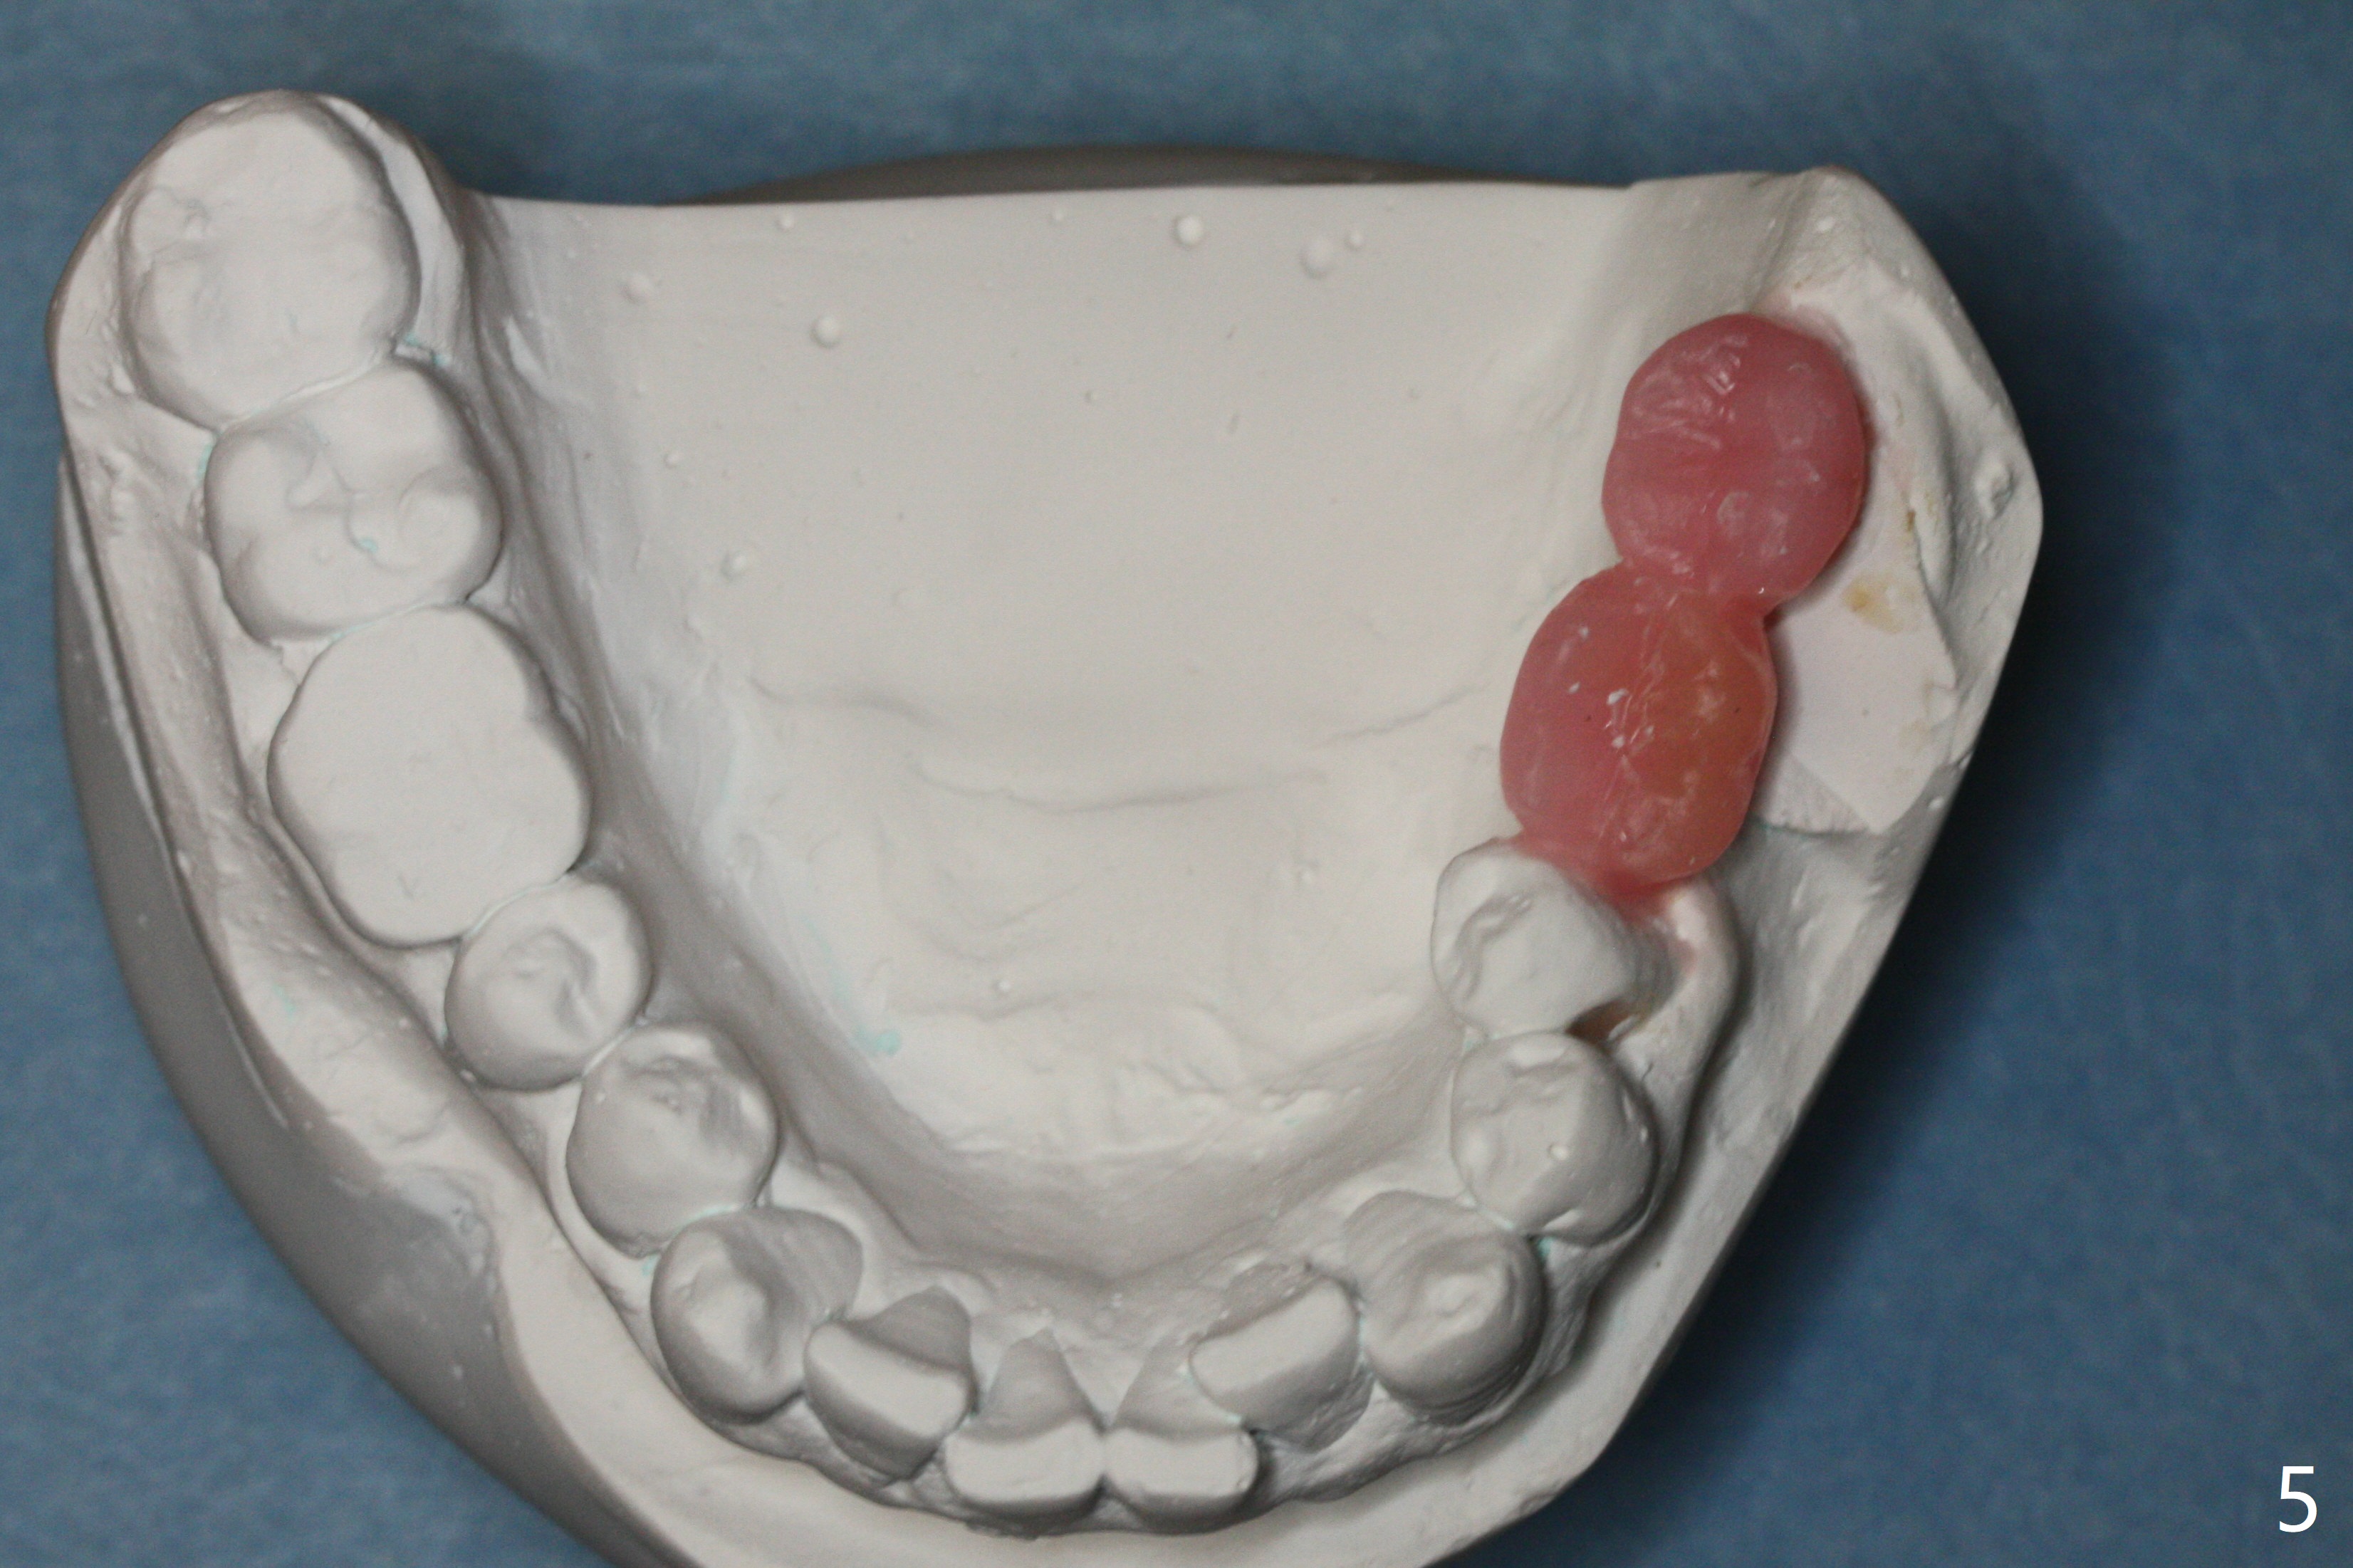

A 43-year-old man has poor dentition on the left: 1st molar missing, 2nd molar mesial inclination (Fig.1) and 2nd bicuspid lingual tilt (Fig.2). The latter is nonfunctional (Fig.3 (linguoposterior view). Two molar implants will be placed in a position so that their crowns will be in cross bite (Fig.4,5), the same occlusal scheme as the teeth #21 and 22. When these implants osteointegrate, the provisional crowns (Fig.6 P) will be supraocclusal so that there is clearance (*) for #20 to upright orthodontically (Fig.7-9). Moreover, these implants will be used anchorage as well as #21 and 22. Panoramic X-ray (Fig.1) and CBCT (Fig.10-12) show limited bone height at the sites of #18 and 19. It appears that 5x8 and 5.9x6 mm implants are appropriate with ridge reduction at #19.